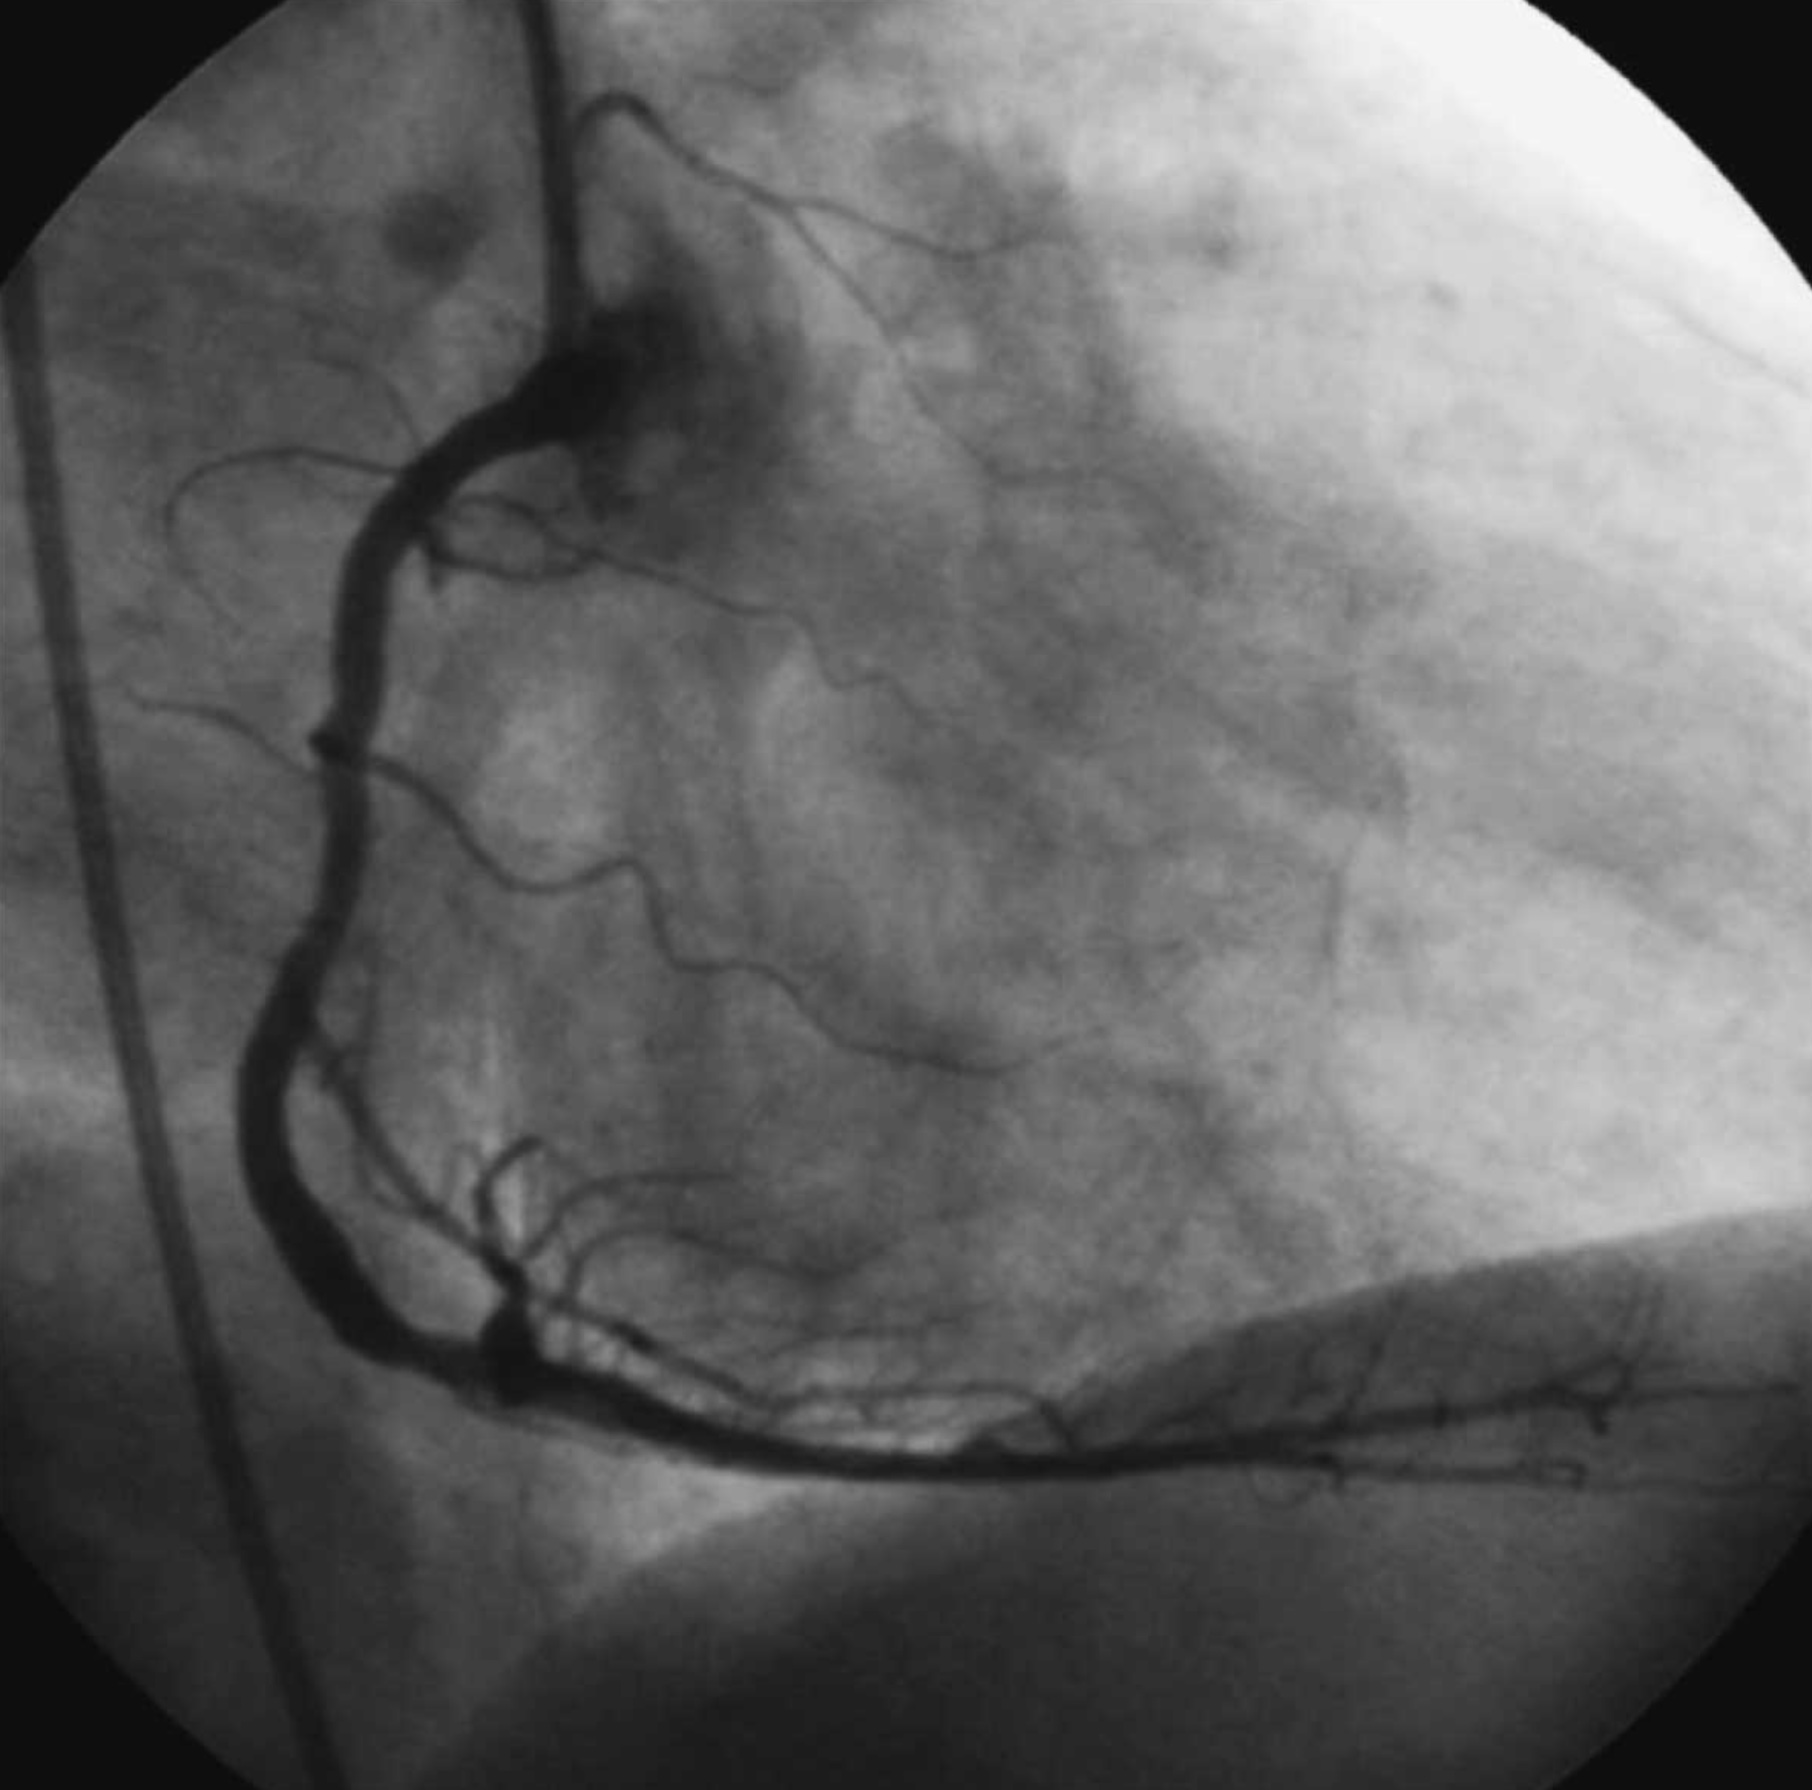

1. An 63 year old man has a heart arrhythmia. Upon further investigation, an angiogram shows an occlusion of the proximal right coronary artery. Why would this potentially cause arrhythmia? Discuss the anatomy and relationships of the right coronary artery and branches as well as the complementary venous drainage. Include mention of any commonly seen anatomical variances, if any.

2. A patient is shown to have a partial occlusion of their anterior interventricular artery (left anterior descending artery). Discuss the anatomy and relationships of the left coronary artery and branches as well as the complementary venous drainage. Why is an occlusion in this artery especially dangerous and what potential surgical solutions can be used as treatment? Include mention of commonly seen anatomical variances, if any.

6. Blockage of the right coronary artery proximal to the sinuatrial branch indicates the need to implant a pacemaker. (True)